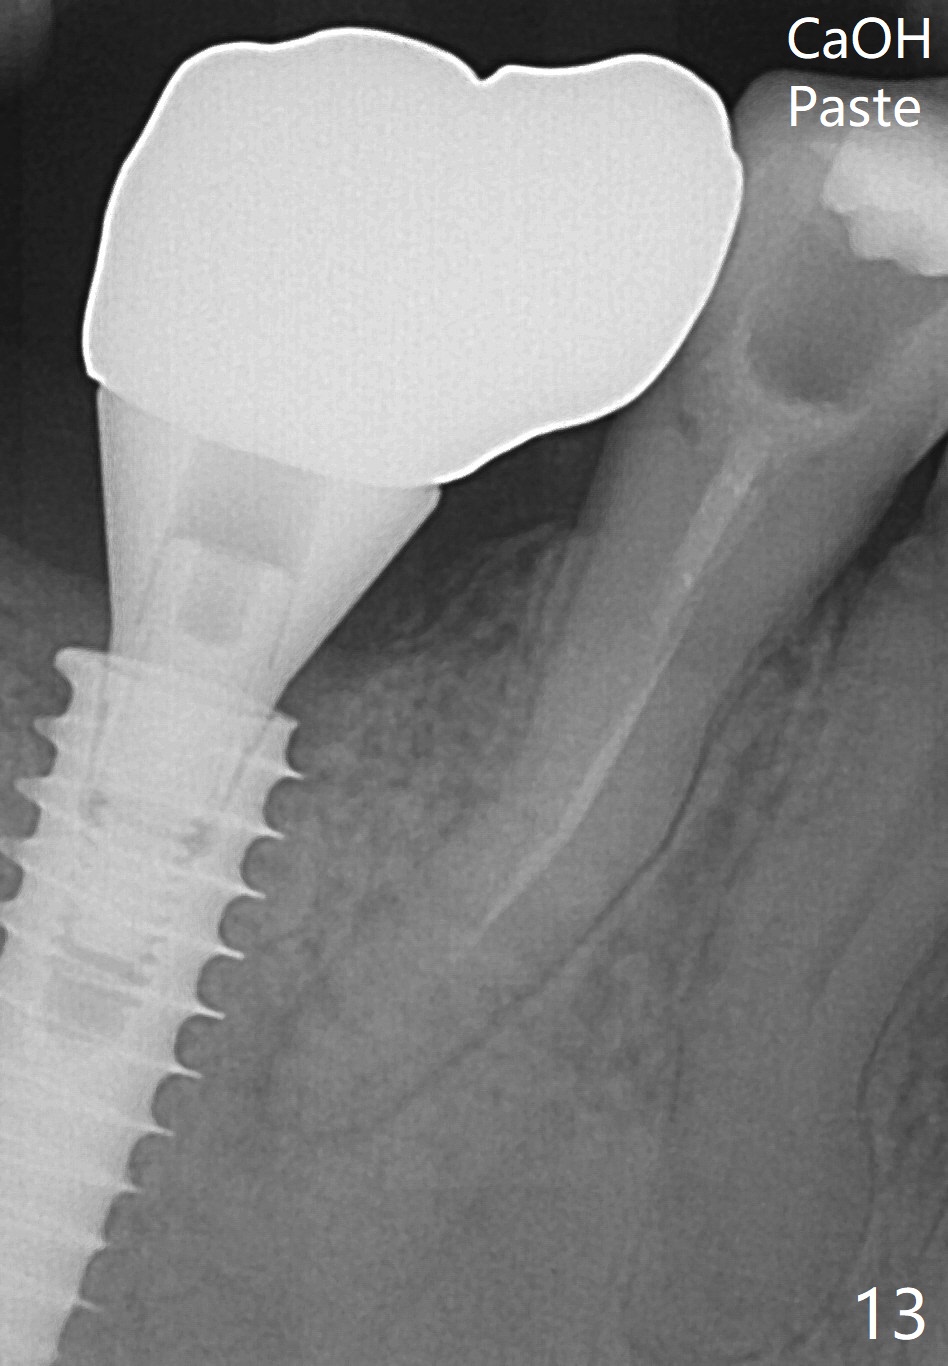

Bone graft seems to sink down and becomes denser 3 months postop (Fig.6 arrow). The bone continues being denser 5 months postop (Fig.7). There is periapical radiolucency of the tooth #29 (^). RCT is done (Fig.8). The pain persists 2 weeks postop (Fig.9,10). There is no missing canal (Fig.9). The apex is close to the implant (Fig.9 *). Apicoectomy will be performed if needed. It appears that the implant is also placed buccal (Fig.10 <) and/or the implant too large for the site. Therefore there should be a 2-3 mm buccal gap before and after implant placement. Separation and reflection of the buccal flap allows better visibility. The pain persists 1 month post RCT and 6 months post implant placement. RCT retreatment is initiated (Fig.11,12) with placement of Calcium Hydroxide paste after redebridement with 30/.04 rotary file at 23.5 mm (.5 mm longer than the earlier RCT, Fig.13). RCT retreatment finishes with apparent transportation and extrusion in 4 weeks (Fig.14,15), followed by apicoetomy (Fig.16,17) (20 days later)). Discomfort remains 2.5 months postop (Fig.18). Keep watching.